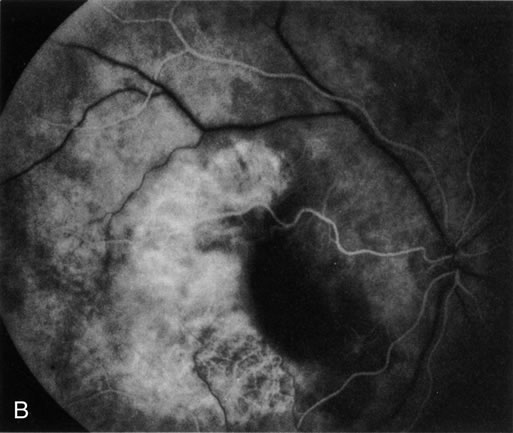

Clinically discernible peripheral dependent bullous neurosensory detachments have been described in patients with chronic CSC.85–92 Yannuzzi and co-workers first characterized the presence of RPE atrophic tracts extending inferiorly in the fundus periphery secondary to antecedent retinal detachment in patients with CSC.85 Presumably, there is a particularly severe and/or longstanding leakage of fluid from an RPE defect in the subretinal space at the posterior pole. The subretinal fluid gravitates inferiorly to form a dependent neurosensory detachment in a “flask,” “teardrop,” “dumbbell,” or “hourglass” pattern (Fig. 31). Sometimes the tract of subretinal fluid connecting the macular detachment with the bullous neurosensory detachment in the inferior hemisphere is so shallow that it is very difficult to appreciate. The RPE under the chronic retinal detachment experiences atrophic changes that appear as atrophic RPE tracts connecting the posterior pole with the dependent retinal detachment. The retina itself develops secondary manifestations including pigment migration, capillary dilatation (telangiectasia) proximally and capillary nonperfusion (ischemia) distally to the area of detached retina (see Fig. 31). The changes in the RPE consist of both RPE atrophy and pigment clumping in the form of perivascular deposits or bone spicules, a condition described by Gass as a “pseudoretinitis pigmentosa–like atypical CSC presentation.”87

Fig. 31. A 47-year-old woman with an18-year history of central serous chorioretinopathy in both eyes. A. Color photograph composite of the left eye shows bullous dependant detachment of the neurosensory retina inferiorly. B. Fluorescein angiogram composite reveals diffuse decompensation of the retinal pigment epithelium, multiple scattered pigment epithelium detachments 9PEDs), and obliteration of the retinal capillaries in the region of the detachments. Note the presence of early neovascularization at the junction between perfused and non-perfused retina. C. Clinical photograph of the left eye shows PED superior to the optic disc partially surrounded by fibrin deposits. D. Fluorescein angiography confirms the presence of active leakage from the serous PED. E, Color photograph composite of the same eye 2 months after laser treatment of the site of leakage reveals partial resolution of the detachment and lipid precipitation. F. Clinical photograph composite 16 months after the laser treatment in the area of the leakage shows complete resolution of the detachment and partial reperfusion of the inferior retina.